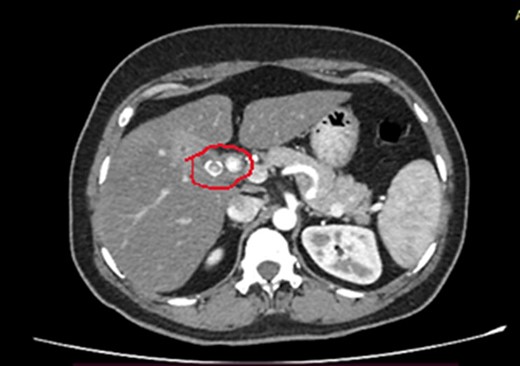

She has undergone a semi-elective ERCP in a semi-prone position, under sedation with propofol target-controlled infusion. Major papillae identified with side viewing endoscopy. Guidewire was inserted into CBD, and a cholangiogram was done. It showed dilated CBD up to 1.3 cm, mild dilated hepatic ducts, and a large radiolucent area in the distal CBD (around 1.5 cm). Sphincterotomy was done with a sphincterotome, and the ampulla was dilated up to 1.5 cm with a balloon dilator. Then, a balloon retrieval was attempted and failed, probably due to a stone sticking to the CBD wall. Then, a mechanical lithotripter was used to break the stone, but it failed, damaging the instrument. During the procedure, her oxygen saturation dropped to 75–80%, and she developed surgical emphysema in the face, neck, and upper chest region. In addition, she developed abdominal distention as well. Immediately, she underwent CBD stenting with a 12-cm, 10 French Gauge double pigtail biliary stent and changed her position to supine. Then, she was intubated with rapid sequence induction, and a nasogastric tube was inserted and transferred to the surgical intensive care unit. Post-ERCP, non-contrast computed tomography (NCCT) of the abdomen and chest showed extensive pneumo-peritoneum and retroperitoneal gas with subcutaneous emphysema (Figs 2 and 3). There was no evidence of air leakage on NCCT and no clinical features of peritonitis on subsequent days. So she was managed non-surgically with nasogastric tube (NG), nil by mouth, intravenous fluids with intravenous antibiotics. Clear fluid was started after 24 hours slowly via NG.

Post-ERCP NCCT abdomen shows pneumo-peritoneum (red arrow), pneumo-retroperitoneum, and subcutaneous emphysema (blue arrow)